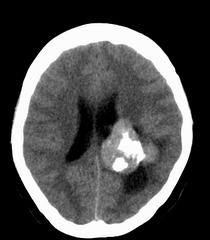

患者,女性,33岁,外伤检查发现,既往没有明显类似病史。

ct平扫见左侧脑室后角不规则形,边界不清的等密度肿块,肿瘤内有钙化,瘤周可见残存的脑室(低密度脑脊液影),考虑脉络脉丛乳头状瘤或室管膜瘤.

左侧脑室内软组织肿物,内部见多发不规则钙化,边界清楚锐利,有分叶。相应左侧脑室扩张。常见的不外乎3种病:室管膜瘤,脑膜瘤,脉络脉丛乳头状瘤。脑膜瘤分叶较少见,脉络脉丛乳头状瘤钙化较少见,因此,室管膜瘤可能性最大。

左侧脑室内见不规则略高密度团块影,边缘分叶,内见多发不规则钙化,病灶与侧脑室壁关系较为密切,左侧脑室扩大。考虑室管膜瘤可能性较大,其次为脑膜瘤,脉络丛乳头状瘤的可能性最小。

左侧侧脑室内分叶状肿块,其内见块状钙化,见左侧脑室阻塞性积水.考虑:脉络丛乳头状瘤

左侧脑室后角不规则形,边界尚清的等密度肿块,肿瘤内有钙化。考虑脑膜瘤或室管膜瘤。